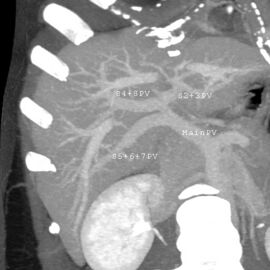

With the recent advances of noninvasive imaging, living liver donors usually have to undergo imaging examinations for liver anatomy to decide if the anatomy is feasible for donation. The evaluation is usually performed by multidetector row computed tomography (MDCT) and magnetic resonance imaging (MRI). MDCT is good in vascular anatomy and volumetry. MRI is used for biliary tree anatomy. Donors with very unusual vascular anatomy, which makes them unsuitable for donation, could be screened out to avoid unnecessary operations.